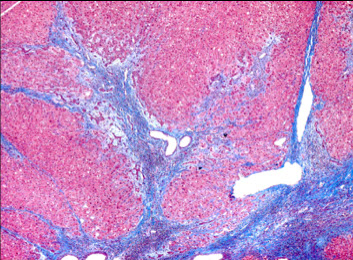

Cirrhosis

Regenerative nodules of hepatocytes surrounded by fibrotic bands

- if nodularity is not complete, may diagnose early cirrhosis

Alcoholic cirrhosis

Caused by recurrent bouts of alcoholic hepatitis, this is the final, irreversible form of liver dz

- liver is micronodular and small from scarring

Sx: Jaundice, edema (hypoalbuminemia)

Micro: sclerosis around central vein (zone III); Councilman bodies (necrotic liver cells); bridging fibrous septa linking portal tracts, fibrosis, parenchymal nodules